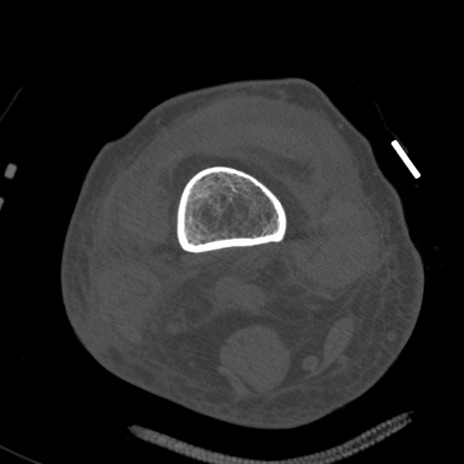

症例28 右膝関節CT(横断像)

右膝関節CT